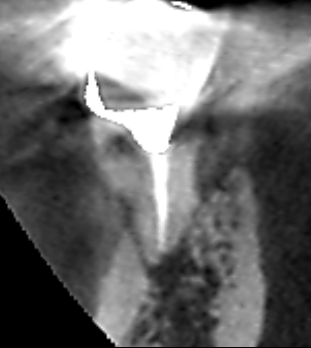

精密根管治療6カ月後の経過観察時の冠状断のCT画像です。下顎第一大臼歯の近心根の根の先にあった膿の影が消失し歯槽骨が再生しています。根管は、フィンを除去・清掃され幅広く拡大されているのが分かります。